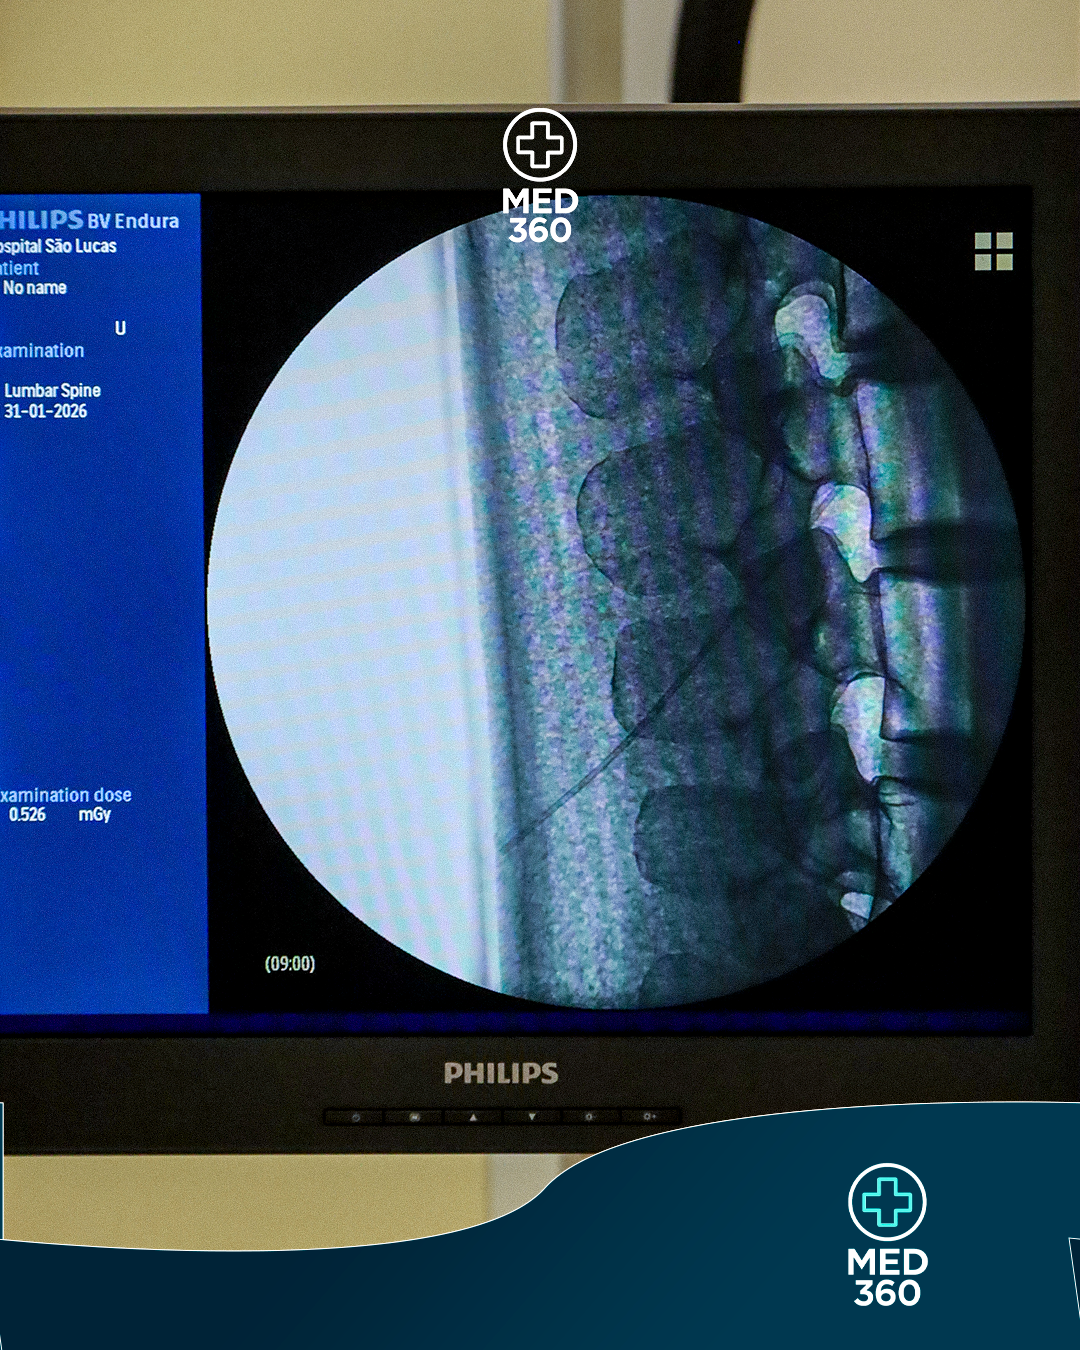

O Dor 360 | Intervenção em Dor na Coluna Lombar foi desenvolvido para médicos e ortopedistas que desejam aprofundar a compreensão dos principais temas relacionados à dor lombar.

O curso reúne conteúdo teórico aplicado, fundamentos de imagem e raciocínio clínico organizado para fortalecer a interpretação dos casos, a avaliação clínica e a tomada de decisão dentro do contexto da dor em coluna lombar.